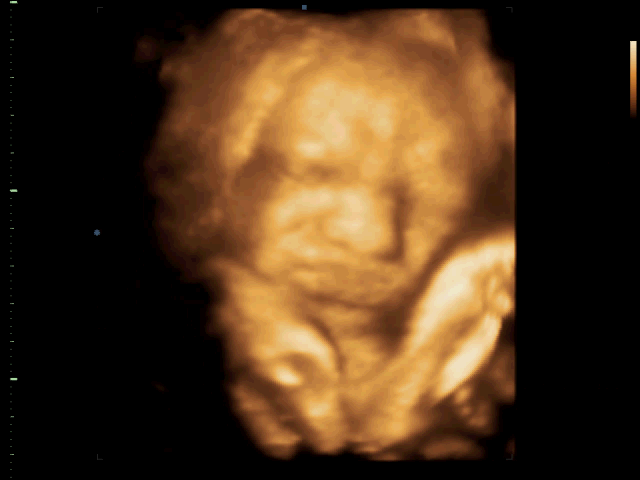

to nansie: Mám fotečky z každé kontroly, i z poslední, je fakt rozkošnej, už aby byl na světě

No to je fešák

. Na první za slušňáka a na tý druhý se krásně kření